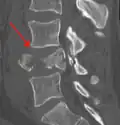

A burst fracture of L4 as seen on plane X ray -

A burst fracture of L4 as seen on CT -

A burst fracture of L4 as seen on CT